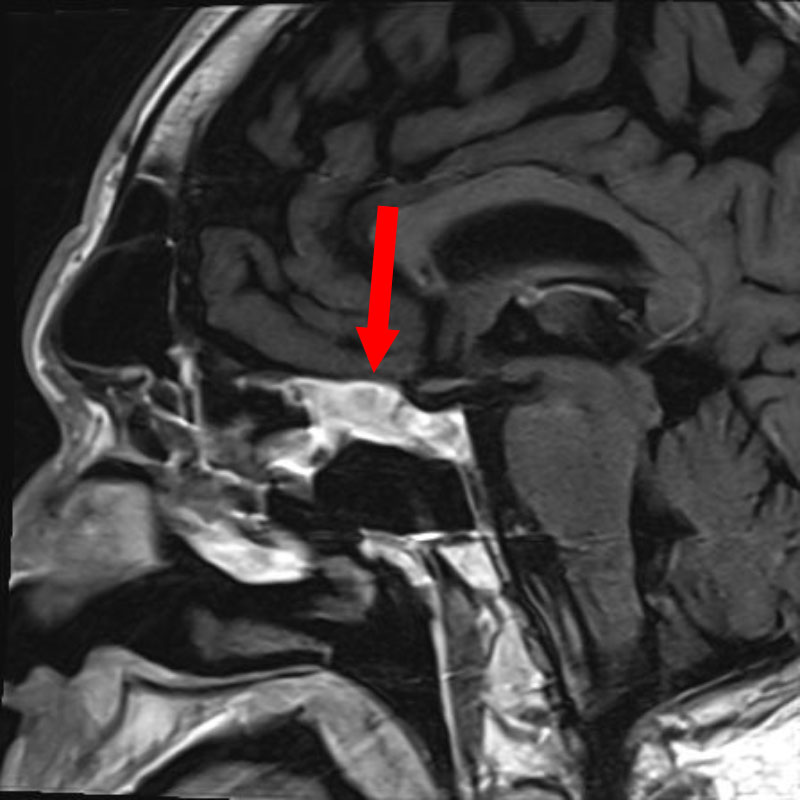

髄膜腫

頭蓋内腫瘍摘出術

No.’25_109 手術前1

No.’25_109 手術前2